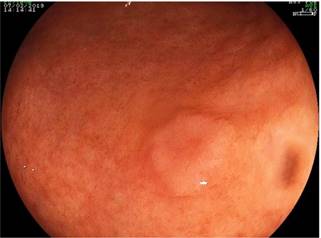

Se presenta el caso de un hombre de 54 años procedente del área rural de Socorro, Santander, a quien se le realizó una endoscopia digestiva alta para la evaluación por un posible cuerpo extraño esofágico, y se encontró como hallazgo incidental la presencia de una lesión de 8 mm en el antro hacia la curva mayor de 8 mm de diámetro, altamente compatible con una neoplasia gástrica temprana 0-Is (Figura 1). Las biopsias fueron compatibles con adenocarcinoma bien diferenciado. Con dichos hallazgos consultó al Hospital Regional Manuela Beltrán, donde se complementaron los estudios con una ultrasonografía endoscópica gástrica, que evidenció el compromiso de las capas ultrasonográficas I y II (hasta la muscular de la mucosa) (Figura 2); por tanto, se clasificó como uT1uN0, compatible con un cáncer gástrico temprano. Como estudios adicionales, una tomografía axial computarizada (TAC) de abdomen contrastada descartó la presencia de metástasis a distancia o compromiso ganglionar. Se programó para realizarle una mucosectomía endoscópica gástrica.